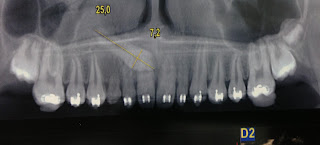

SEGUNDO PACIENTE:

RADIOGRAFÍA CONVENCIONAL PANORÁMICA DONDE SE OBSERVA CANINO IMPACTADO Y EN MALPOSICION PARA ERUPCIONAR